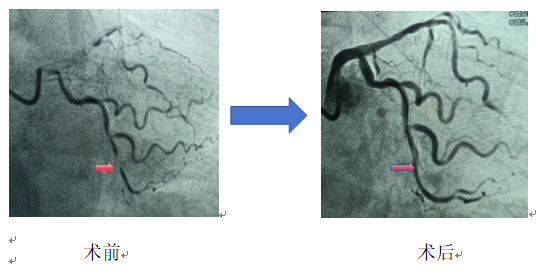

35岁的李先生,长期吸烟,突发胸痛1小时来海慈医疗北院区急诊科就诊,心电图检查发现急性下壁心肌梗死,病情危急!北院区立即启动导管室,心血管内科(含CCU、老年科)主任范广慈为患者紧急实施冠状动脉造影,显示患者左回旋支中段完全闭塞,开通闭塞冠脉后,综合患者年龄、病变部位的血管直径、血栓负荷情况及IVUS(血管内超声成像检查)结果,在对病变充分预处理后,对患者病变部位进行了药物球囊扩张处理,取得了满意的效果。目前患者病情恢复良好,定期随访中。